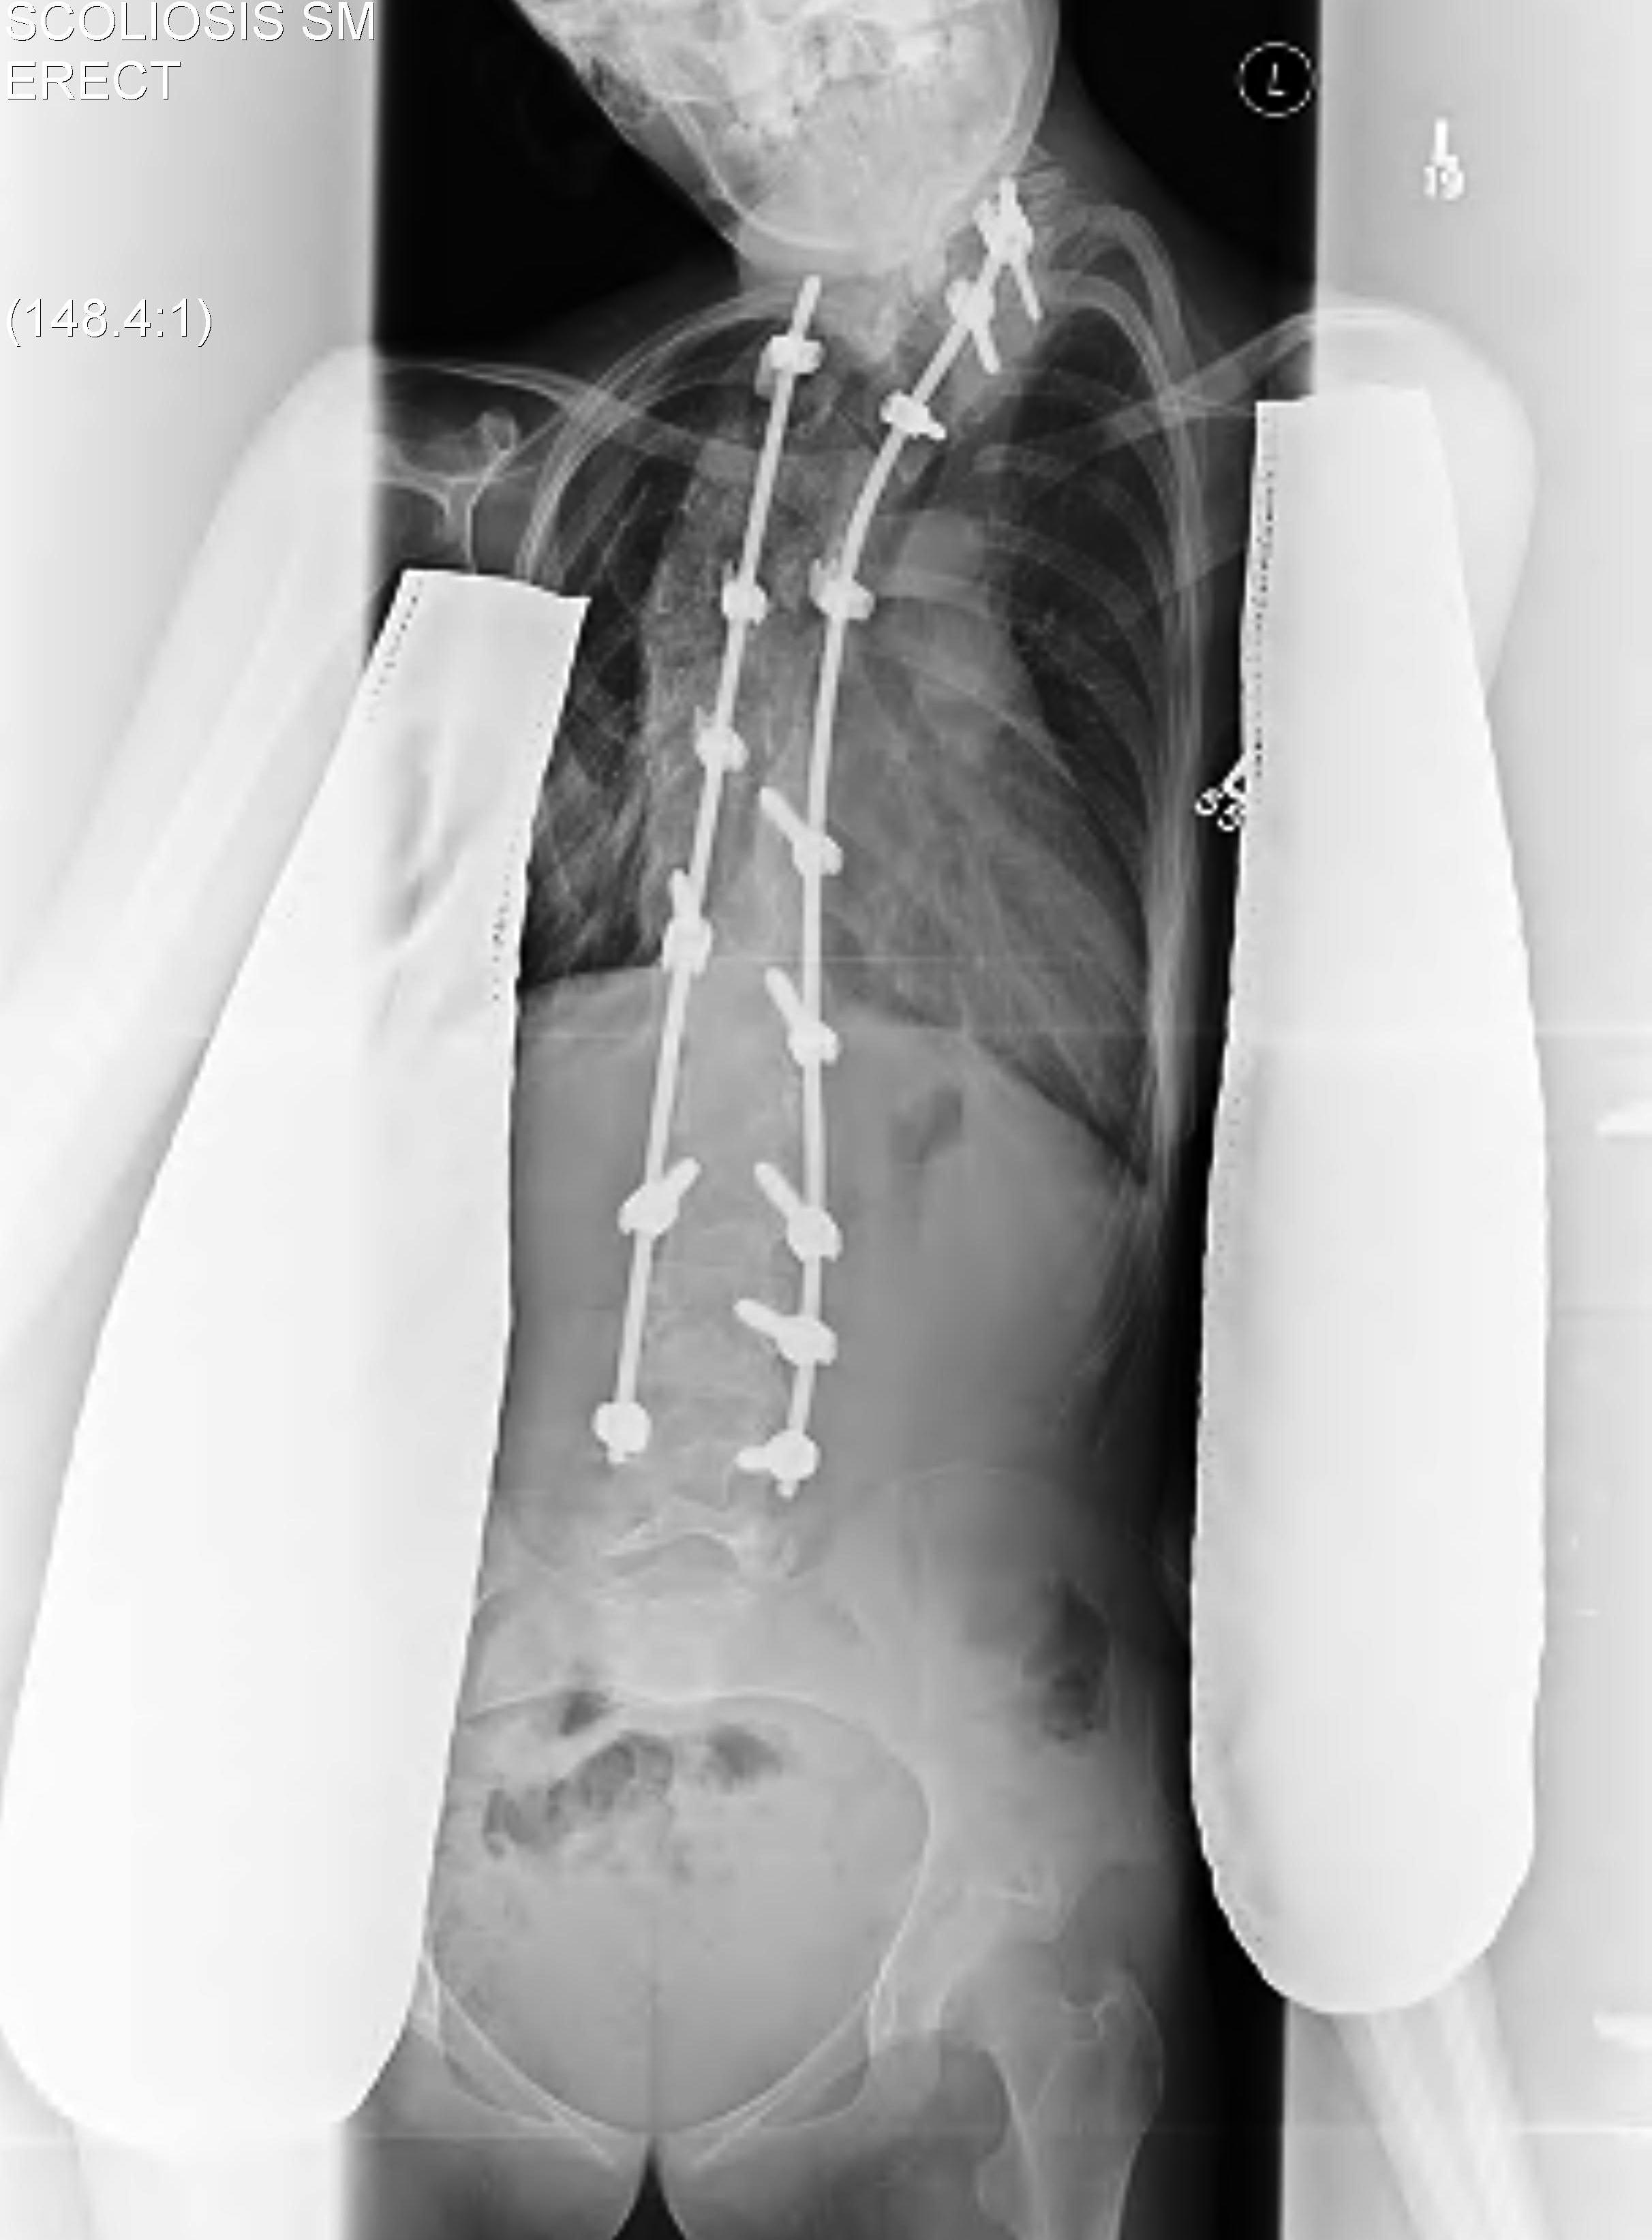

Surgery

Solid arthrodesis of balanced spine over level pelvis

Long, solid fusion from upper thoracic to lower lumbar

Rigid instrumentation & massive bone grafting

Instrumented fusion

- proximally from T3 or T4 to prevent later subsequent deformities

- caudally to pelvis if >15° pelvic obliquity

- to L4 or L5 if balanced

- often need sublaminar wires for large C shaped curve

- place in midcurve to pull spine to the rods

- large fusions require allograft